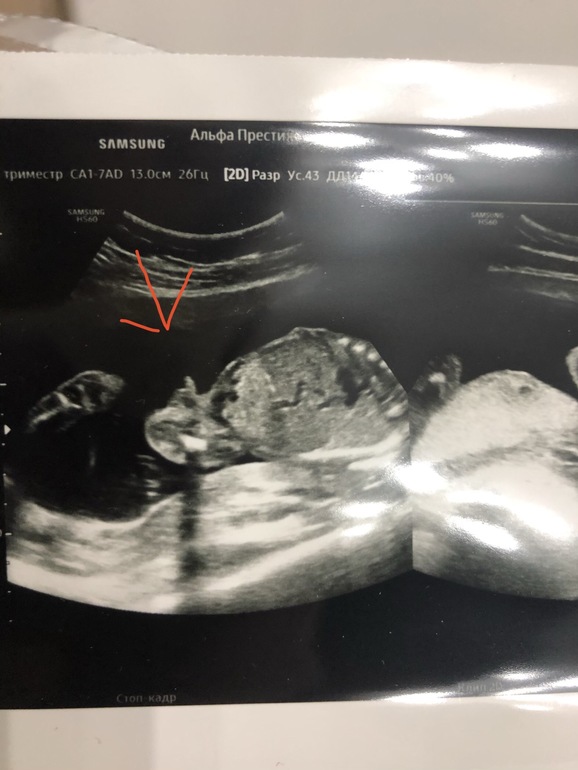

Кажется девчуля🥰у нас прям на узи перчик было видать лучше всех остальных частей тела 😀👍🏻

Я ж такая же кума 😀😀🤦♀️И коляску и шмотки розовые все искала смотрела , а тут дратути кстати нашла фотку с узи с писюнчиком😀😀мы как увидели с мужем сразу поняли , узист и слово сказать не успел😀😀вам наверное ещё узи делали не стали заморачиваться в ракурсах смотреть пол и сказали скрининг ждите)

Ну тут у вас прям реально пипирка такая, все сразу понятно 😂 мне узи ещё делали на таком допотопном аппарате, порой не понятно че так такое показывает 😂